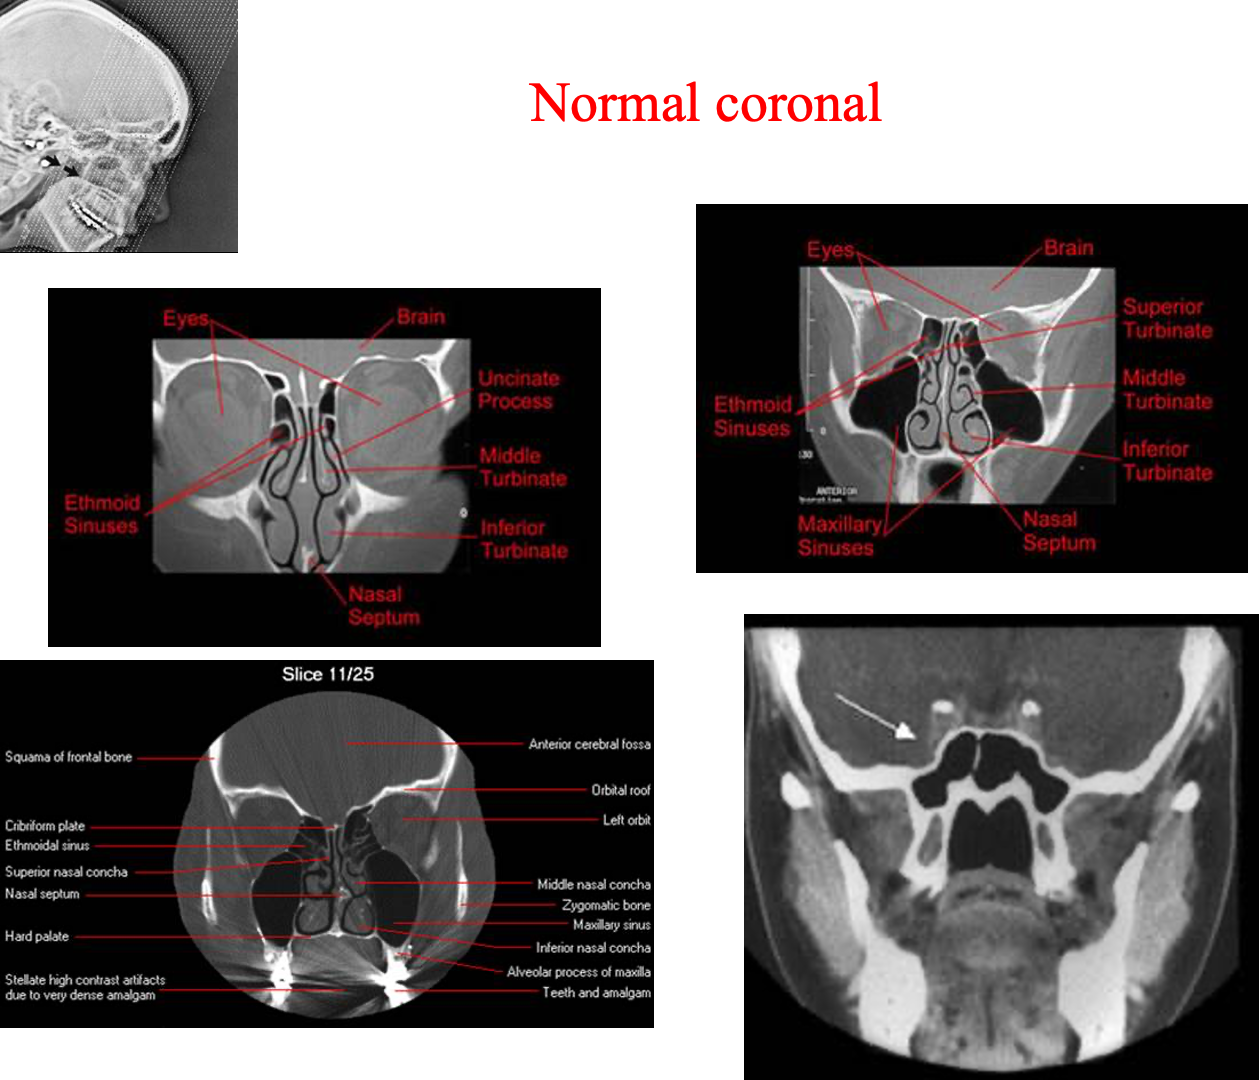

CT Paranasal Sinuses

- Axial

- Coronal